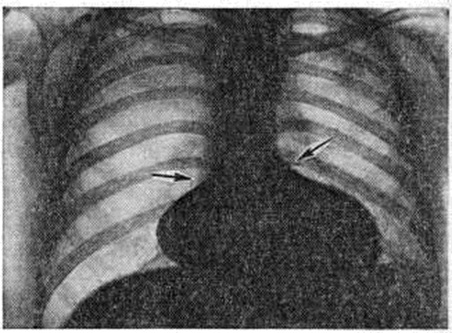

Рентгенограмма грудной клетки при аортальном стенозе: тень сердца имеет форму башмака (аортальная конфигурация) с увеличенным левым желудочком; (указан стрелкой), верхушка закруглена (гипертрофия левого желудочка).

При рентгенологическое исследовании у детей тень сердца нормальных размеров или с признаками гипертрофии левого желудочка. При высоком конечно-диастолическом давлении в левом желудочке и левом предсердии отмечаются застойные явления в прикорневых отделах лёгких. Может быть расширена восходящая часть аорты (постстенотическая дилатация). У детей с выраженным стенозом рентгенологически определяется аортальная конфигурация сердца (рисунок 4) и усиленный легочно-сосудистый рисунок.